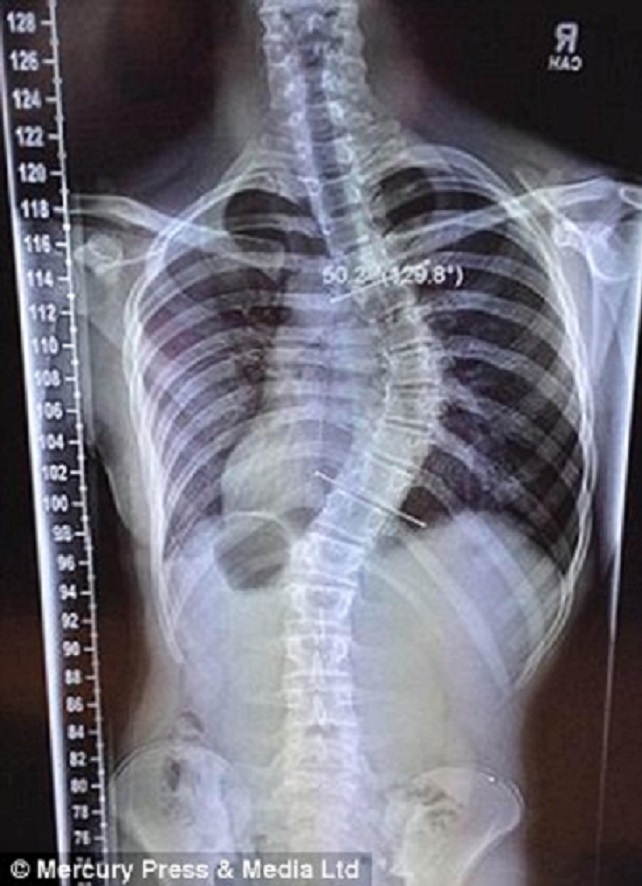

Năm 2014, chiều cao cơ thể Lauren tăng thêm 15 cm chỉ trong vòng hai tháng. Đây là một đòn nặng nề đối với ước mơ cạnh tranh trên đấu trường quốc tế của Lauren. Chiều cao tăng quá nhanh khiến cột sống của cô cong 45 độ, giống như quả chuối.

| Xương sống của Lauren vẹo 45 độ. Ảnh: Mercury Press & Media Ltd |